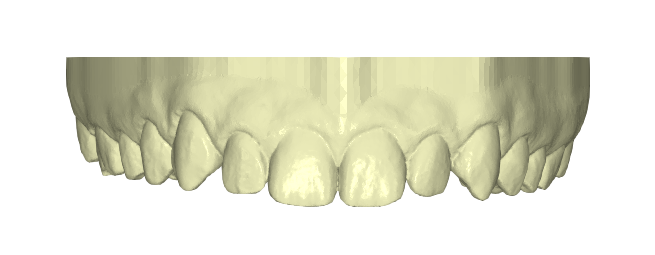

Paciente joven que acababa de finalizar su tratamiento de ortodoncia. Aunque estaba satisfecho con el resultado general, no se sentía cómodo con las troneras incisales que habían quedado entre los laterales y los caninos. Buscaba una solución rápida, estética y mínimamente invasiva

Desde Elevantia Solutions propusimos un Injectable Composite Design con carillas únicamente en esas piezas, para cerrar los espacios sin necesidad de limar sus dientes. Se trabajaron varias versiones del diseño hasta conseguir un resultado totalmente adaptado a sus expectativas, respetando al máximo la estructura dental natural al cerrar los espacios